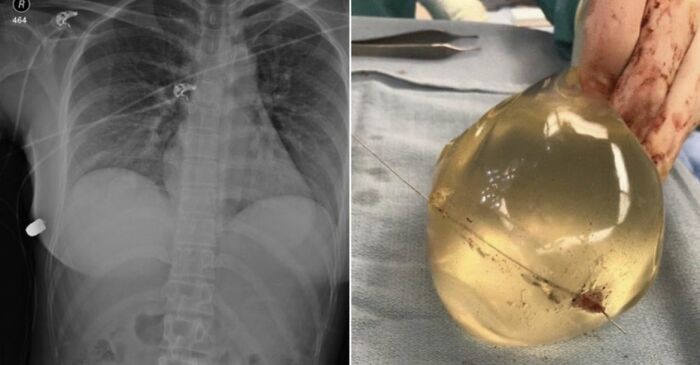

En 2018, unos implantes mamarios de silicona salvaron a una mujer de una bala disparada a quemarropa en Canadá. Los médicos observaron que el implante desvió la trayectoria de la bala, salvando así la vida de la mujer. Sus únicas heridas fueron una costilla fracturada. Sus órganos vitales no sufrieron daños.